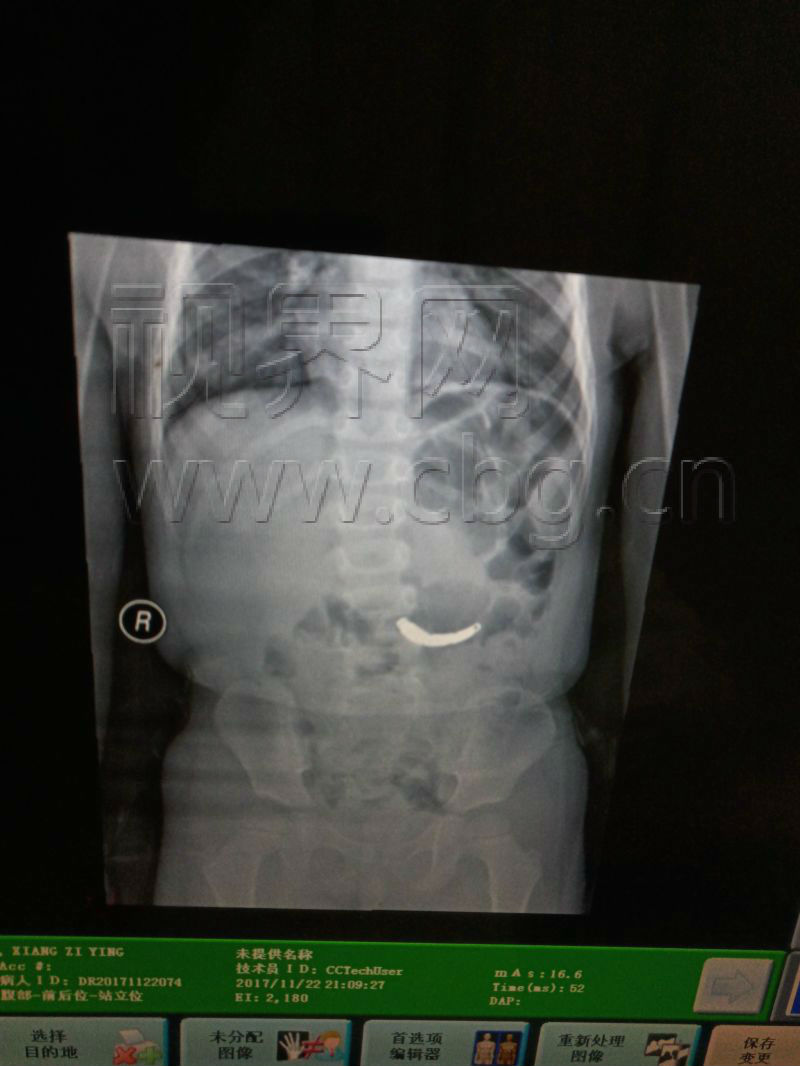

这两天,万州市民王先生(化名)差点急坏了。22日早上,王先生(化名)在给女儿兑奶粉时候,2岁女儿误将他取下的不锈钢手表带吞下,情况危急。事情发生后,王先生急忙将女儿送医救治。医生称,若表带进入胃中,可做胃镜取出,最坏的打算是做手术。

今天上午11点半,医生通过胃镜将表带取了出来,王先生悬着的心总算落地。记者提醒家长,金属类小件物品请放在孩子触不到的地方,避免发生意外。(来源:视界网)